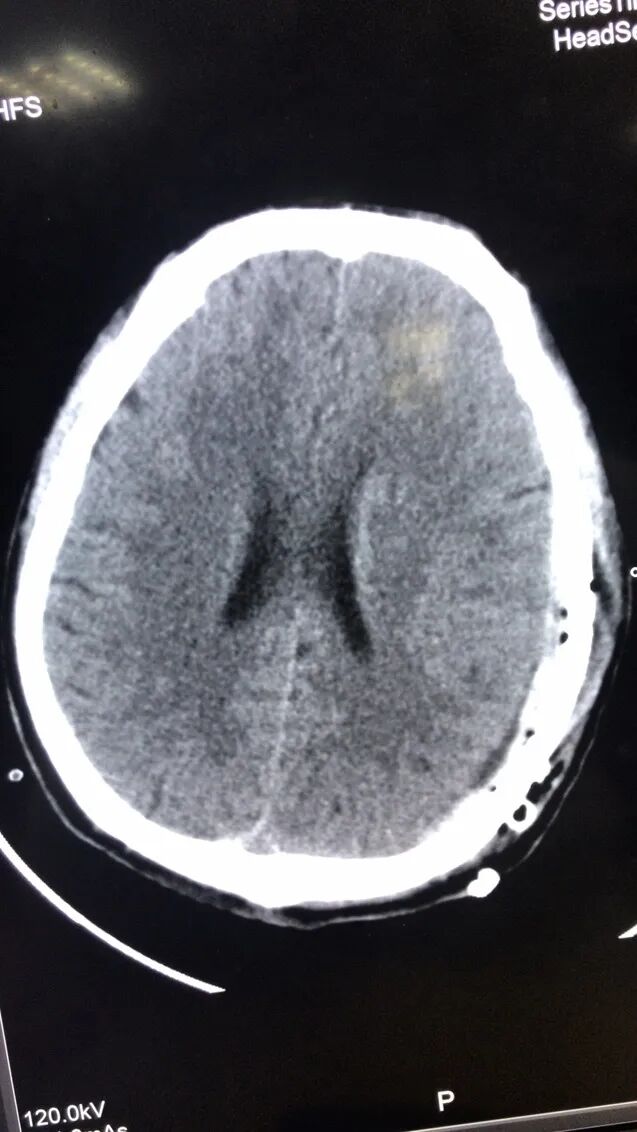

经过CT检查,陈师傅顶部硬膜外血肿,顶骨骨折,同时左侧多处肋骨骨折,情况危急,急症检查完后就立刻转入ICU救治。经过ICU和神经外科联合救治,陈师傅目前已经恢复了意识,是否已经脱离危险,还需要进一步观察。

手术前